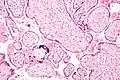

Micrograph of CMV placentitis.